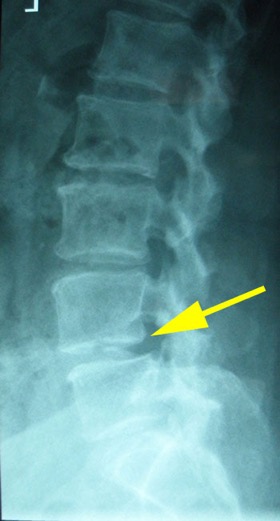

The new MRI was NORMAL. The previously reported large L4-5 disc was completely resorbed. (see picture below)

CT was ordered and shown Spinal Canal Stenosis at L4 5, and a left-sided disc prolapse with impingement of the left L4 root.